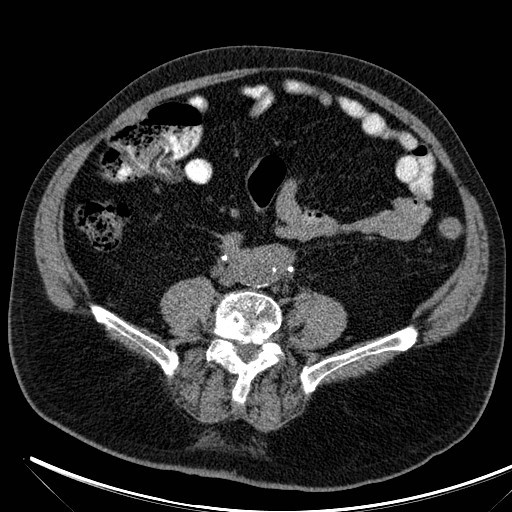

Interventional angiogram identified her primary bleeding source from the left circumflex iliac artery a branch of the external iliac artery and also to a lesser degree from the left L4 and L5 lumbar arteries.

Case Discussion

The patient was emergently transferred to a tertiary center for endovascular embolization. Endovascular angiography revealed the above primary bleeding sources. Each artery received Onyx embolization. Immediate post embolization images showed satisfactory control however her time in ICU continued to be turbulent with dependency on vasoactive medications and continued transfusion of blood products. Repeat abdominal CT angiogram confirmed an increase in the size of her retroperitoneal hematoma. The patient continued to deteriorate falling into multiorgan dysfunction syndrome thought to be contributed by abdominal compartment syndrome. An emergency midline laparotomy was performed. The massive hematoma was evacuated with a rough calculated volume of 10 L. No active arterial bleeding was identified, perhaps from the massive hematoma achieving tamponade. Fortunately, the patient made a full recovery.

Case courtesy of Dr Paul Clarke, Radiopaedia.org, rID: 69556